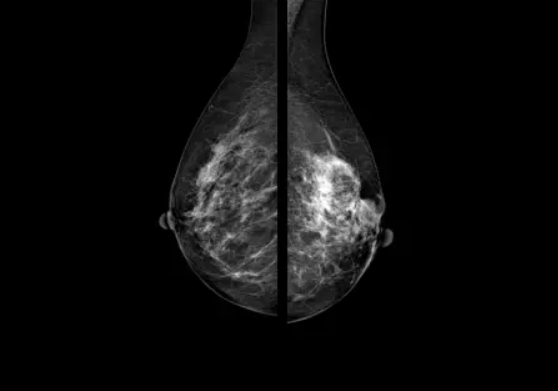

Снимки, получаемые с помощью искусственного интеллекта DIAR-MAMMO

Программное обеспечение использует интеллектуальные алгоритмы нейронных сетей и эффективный приемник для анализа получаемых геометрических данных о размере, плотности и оптимальной компрессии молочной железы, благодаря чему полученные изображения позволяют увидеть мельчайшие очаги поражения ткани молочной железы.

Система определяет плотность ткани молочной железы по АСВ и присваивает исследованию категорию ВI-RADS.